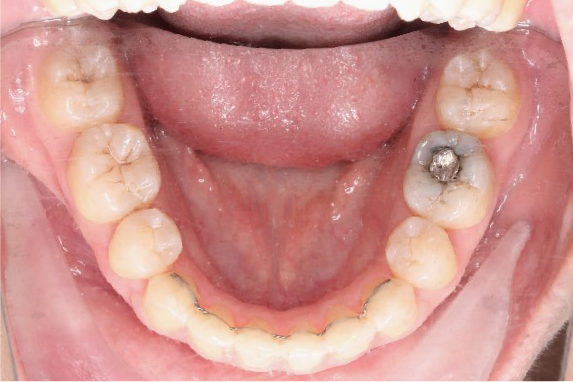

2018.11.14  术后磨牙尖牙I类关系,中线齐,覆合,覆盖正常

牙根基本平行,未见牙根吸收

微观评价:牙齿整齐,咬合关系良好,上下前牙转矩及突度控制良好,磨牙关系I类,尖窝咬合关系良好,OB,OJ正常。